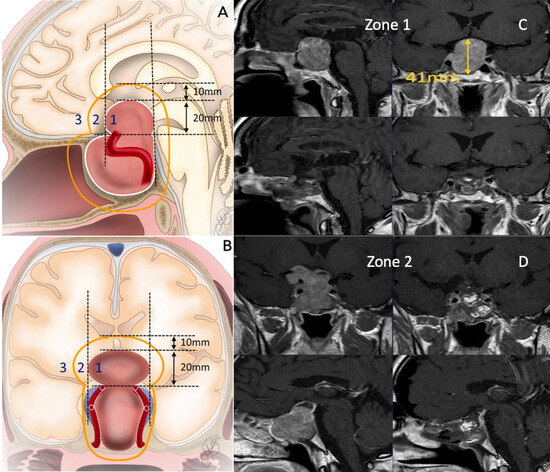

| Zone | <0.001 | ||||

| 1 | 8 (16.3) | 0 (0) | 0 (0) | 8 (47.1) | |

| 2 | 21 (42.9) | 5 (35.7) | 10 (55.6) | 6 (35.3) | |

| 3 | 20 (40.8) | 9 (64.3) | 8 (44.4) | 3 (17.6) | |